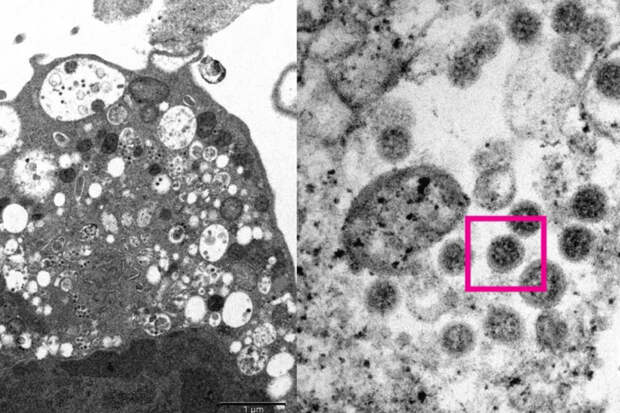

Университет Гонконга опубликовал сразу две микрофотографии омикрон-штамма коронавируса, снятые в клетке почки обезьяны — одну при малом, а другую при большом увеличении.

Ученые медицинского факультета использовали для съемки электронный микроскоп. На микрофотографии видно повреждение клеток с набухшими везикулами, содержащими маленькие черные вирусные частицы.